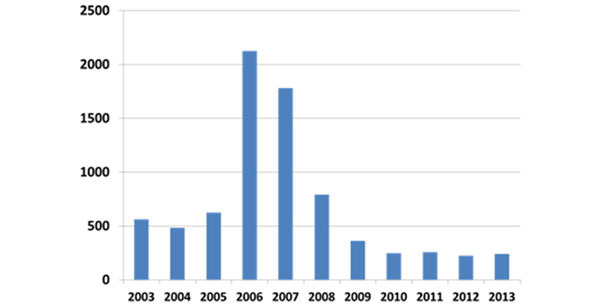

W czasie kiedy PCVAD przybrała formę epidemii (2004-2007), straty związane z chorobą i warchlaków i tuczników sięgały niekiedy 40% co doprowadziło w USA zmniejszenia liczby ubijanych świń o prawie 10%. Na początku 2006 roku producenci poszukiwali skutecznych narzędzi walki z PCVAD. Mimo, że wiele grup naukowców miało dobre wyniki w opracowywaniu nowych szczepionek w końcu lat 1990-tych, pierwsza komercyjna szczepionka pojawiła się w 2006 roku a stosowanie szczepień upowszechniło się w latach 2007-2008. Szczepionki przeciw PCV2 okazały się niezwykle skuteczne, zarówno w zapobieganiu stratom związanym ze śmiertelnością i wyniszczeniem, jak i powodując ogólnie lepsze i wyrównane przyrosty. Efekty działania skutecznej immunoprofilaktyki przy pomocy szczepionek w zwalczaniu strat obserwowane są do dziś. Trendy w diagnostyce PCVAD zilustrowany na rycinie 2.

Ryc. 2: Częstość wykrywania PCVAD (ISU VDL)

Obecnie skuteczność szczepionek przeciw PCVAD jest niepodważalna i niemal wszystkie świnie produkowane w USA są szczepione. Ponieważ jednak PCV2 stale utrzymuje się szczepionych populacjach niekiedy dochodzi do występowania PCVAD.